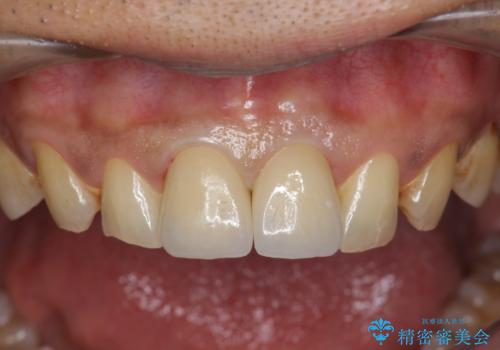

歯ぐきからの出血 膿が出る 前歯根管・セラミック治療

- 46万円(仮歯・根管治療・ファイバーコア・ジルコニアクラウン×2)費用は治療当時の料金となります

X線検査や歯周組織検査などを行い適切な治療を行うことで良好な結果を得ることができます。